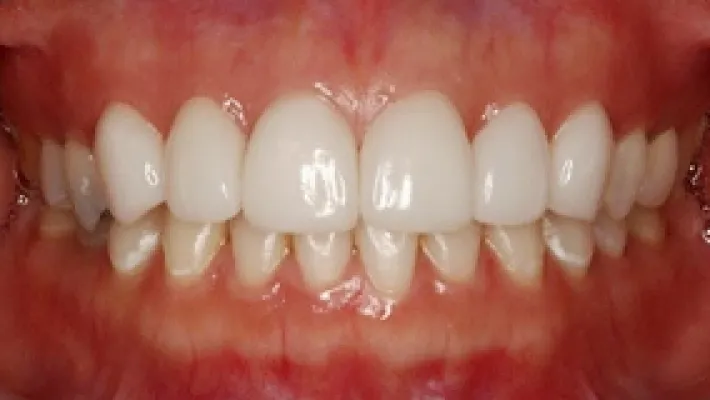

施術前

施術後

マウスピース矯正の部分矯正で上下前歯のすきっ歯を改善した症例です。

状態にもよりますが、すきっ歯はマウスピース矯正の得意とするケースの一つです。

効率的な治療計画で最小限の期間と負担で矯正を行いました。

矯正治療の期間・方法

矯正治療の期間や方法は歯並びや顎骨などの状態によって大きく異なります。

矯正治療は歯や歯周組織などに必ずダメージがあります。

矯正治療のダメージを最小限にするために健康的で現実的な治療計画を提案します。

治療費

470,000

治療期間

6.5ヶ月